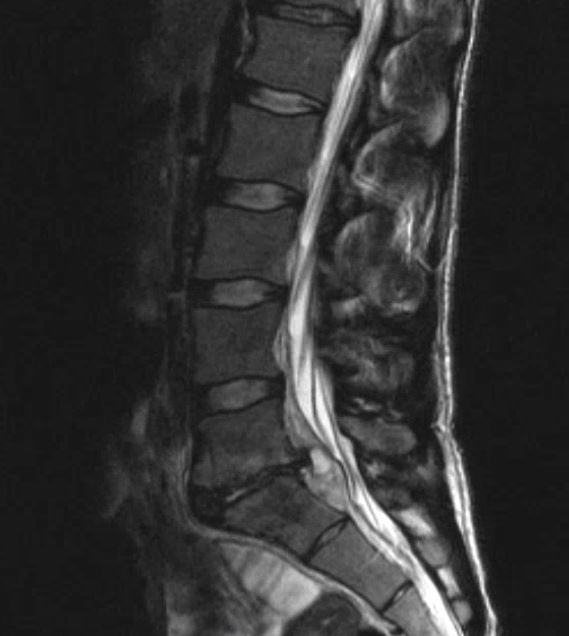

What’s the Diagnosis? Gepost op 12 januari 2020 door netwerkvsseh What’s the Diagnosis? By Dr. Loran Hatch @emdaily.cooperhealth.org Dit delen: Delen op X (Opent in een nieuw venster) X Share op Facebook (Opent in een nieuw venster) Facebook Delen op LinkedIn (Opent in een nieuw venster) LinkedIn E-mail een link naar een vriend (Opent in een nieuw venster) E-mail Afdrukken (Opent in een nieuw venster) Print Vind-ik-leuk Aan het laden... Gerelateerd